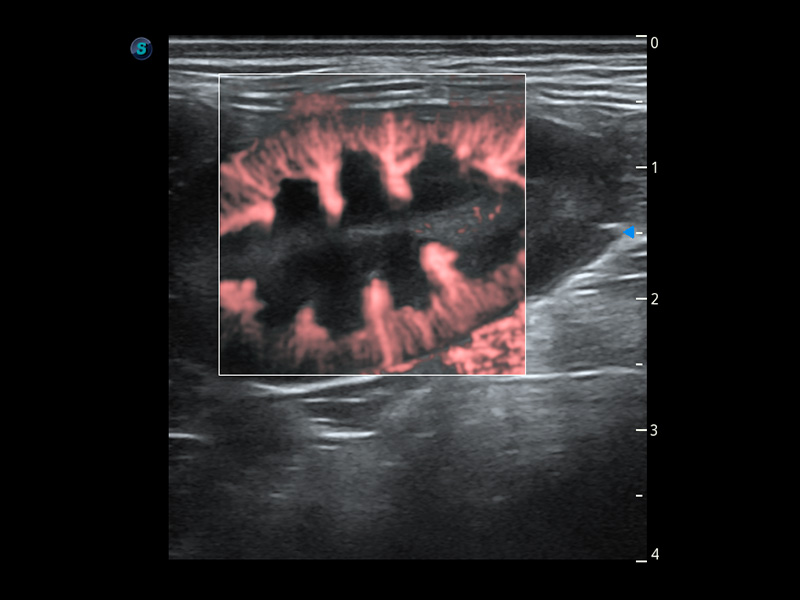

PDI 能量多普勒血流

提供高灵敏度和空间分辦率的血流图像,获得更加真实和丰富的诊断信息。

Bright Flow 立体血流成像

在传统二维血流成像的基础上,呈现血流的立体感,具有动感的生命力之美。精确区分不同血管的空间关系,提高了血流的视觉敏感性。